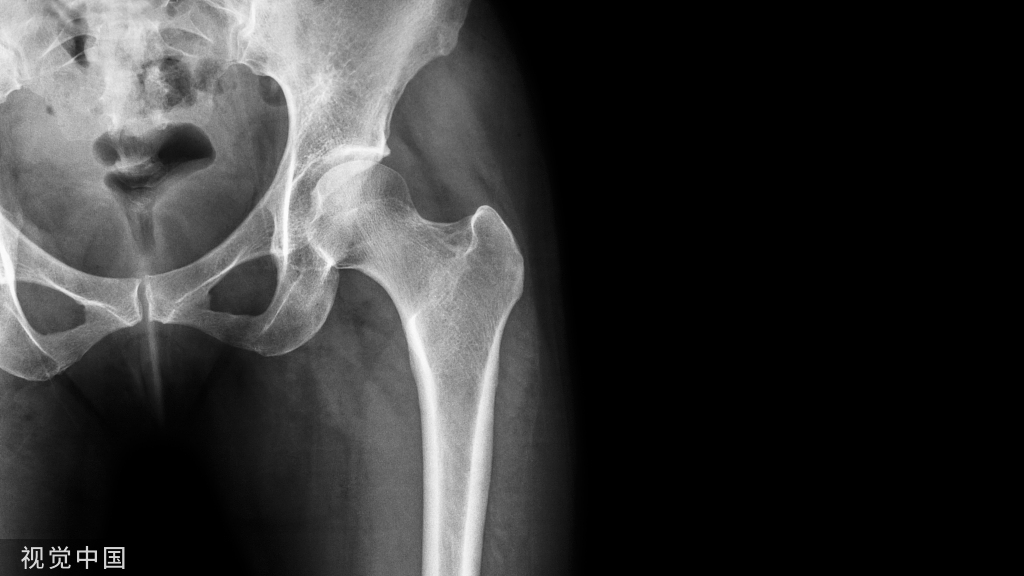

【普通放射图片】:

【影像表现】:X线髋关节正位(A)和膝关节正位(B)显示关节间隙变窄,关节边缘骨赘形成【影像诊断】:关节退行性变。